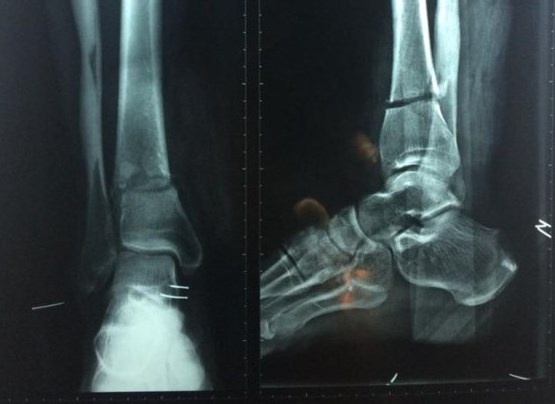

| Phim chụp X-quang cho thấy chân phải ông Châu gần đứt lìa sau khi bị dao máy cắt cỏ chém. Ảnh: Hòa Khánh |

Bác sĩ chẩn đoán chân phải ông Châu bị đứt động mạch và thần kinh chày sau, đứt toàn bộ gân cơ mặt sau. Ê-kíp rửa vết thương, cắt lọc phần dập nát và thực hiện vi phẫu nối động mạch, thần kinh.